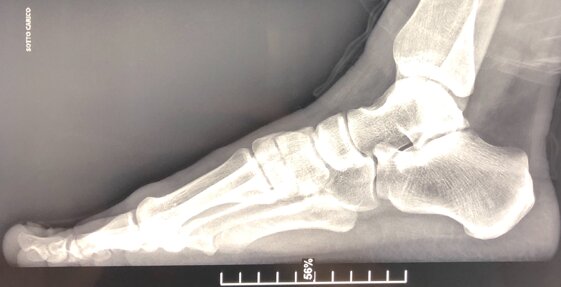

In alto a sinistra foto pre-operatoria del piede da operare affetto da cisti dorsale I MT-F ed esostosi dorsale testa I MT.

In alto a destra radiografia pre-operatoria sotto carico in LL che evidenzia la presenza dell’esostosi dorsale della testa del I MT causa del dolore nella deambulazione e nel calzare le comuni calzature.

In basso a sinistra radiografia post-operatoria in LL di intervento di asportazione cisti dorsale I MT-F ed asportazione esostosi dorsale testa I MT